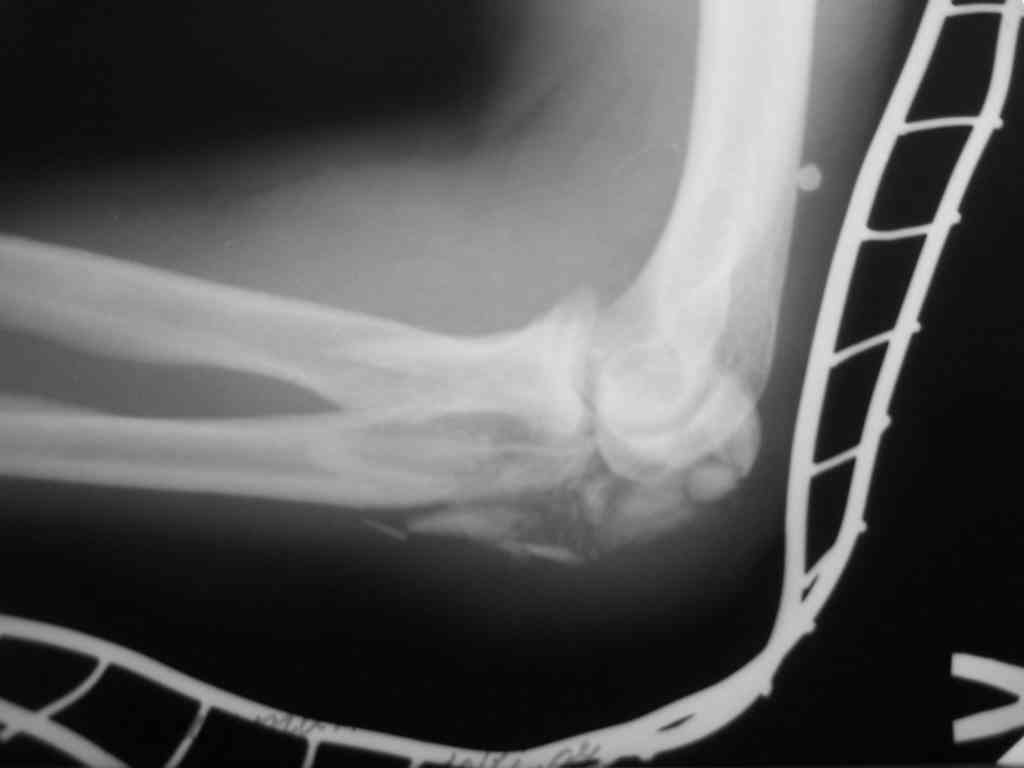

Снимки вот еще какие есть (наши лаборанты пытались сделать что то)

|

При самом большом к Вам уважении, Сергей Анатольевич, не соглашусь. У меня, после того, как добавили "прямой" снимок, сомнений не осталось. Венечный сломан наверняка. Но чтобы судить, насколько это критично для стабильности, нужно иметь строго боковую проекцию. И при этом помнить, что на него крепятся медиальные связки.

Прикрепляю снимок, где обведен фрагмент, несущий на себе венечный отросток (весь он смещён с этим фрагментом или частично - без качественной боковой проекции судить сложно), и отдельно на снимке обведено "ложе", от которого он сместился.

Здесь выставлены несколько случаев и варианты фиксации локтевого отростка, некоторые в комбинации с другими переломами.

3 вариант

перелом с capitelum humerus и проксимальной трети улна